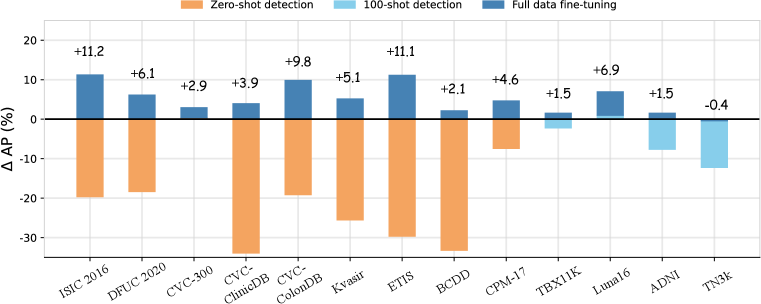

Transfer performance surpassing supervised methods To prove that text prompts are effective for cross-domain transfer, we conduct extensive experiments under both zero-shot domain transfer and supervised transfer (fine-tuning) settings. We include a series of supervised baselines: FasterRCNN, RetinaNet, and DyHead-L for comparisons. As illustrated in Figure 2, our full data fine-tuned models with well-designed medical prompts (dark blue) surpass the supervised baseline (e.g., DyHead-L in the figure) by a large margin across all datasets. Moreover, even zero-shot (brown) or 100-shot (sky blue) results on some datasets, e.g., CVC-300 and Luna-16, can rival the full data fine-tuned supervised models. The quantitative numbers are respectively shown in Table 2 for non-radiology datasets, Table 3 for polyp datasets, and Table 5 for radiology datasets. This is also supported by Figure 3 (right) where the VLMs significantly outperform the classical detection models with fully supervised learning, especially in few-shot settings.

The effectiveness of attribution injection and auto-prompts In section 3.2, we discussed that adding attributes could make the models perform better in zero-shot tasks. Here, we demonstrate in Figure 3 (left) an overall pattern of the effect of attribute injection on performance under the zero-shot setting. As shown in the figure, the overall performance increases as more attributes are integrated into the prompts. This is also illustrated in Table 4 on the BCCD dataset, where various attributes and their combinations are shown to improve the results. As this process is rather tedious and time consuming, we need qualified automatic approaches to accelerate the generation process to scale up without sacrificing too much performance. Fortunately, the models with our proposed auto-prompts, especially with the hybrid and MLM-driven approaches, show comparable results to those with manually created prompts and surpass those with default prompts by a landslide. For example, the MLM-driven approach achieves an AP of 24.8% for zero-shot on the DFUC2022 dataset, while the GLIP-T baseline with default prompts only gives 0.1% for the zero-shot performance (Table 2). Figure 4 shows an example of the auto-prompt generation with the hybrid approach.